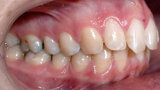

ClearCorrect treatment of crowding